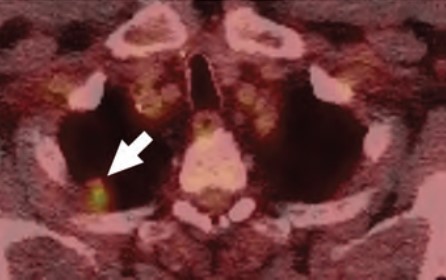

At the individual level, some of the barriers to awareness include unfamiliarity with LCS as a health preventive service tool (Fig. 2), unawareness of the new USPSTF and Centers for Medicare & Medicaid Services (CMS) recommendations for LCS, unfamiliarity with insurance coverage and costs, uncertainty about available accredited LCS programs, lack of culturally appropriate information, and lack of information at an appropriate health literacy level [8–10].